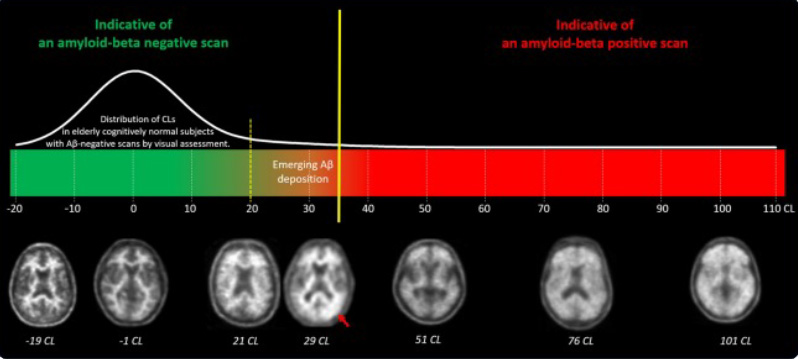

Note: the 20-35 range (the region between the yellow lines) is considered “intermediate.”